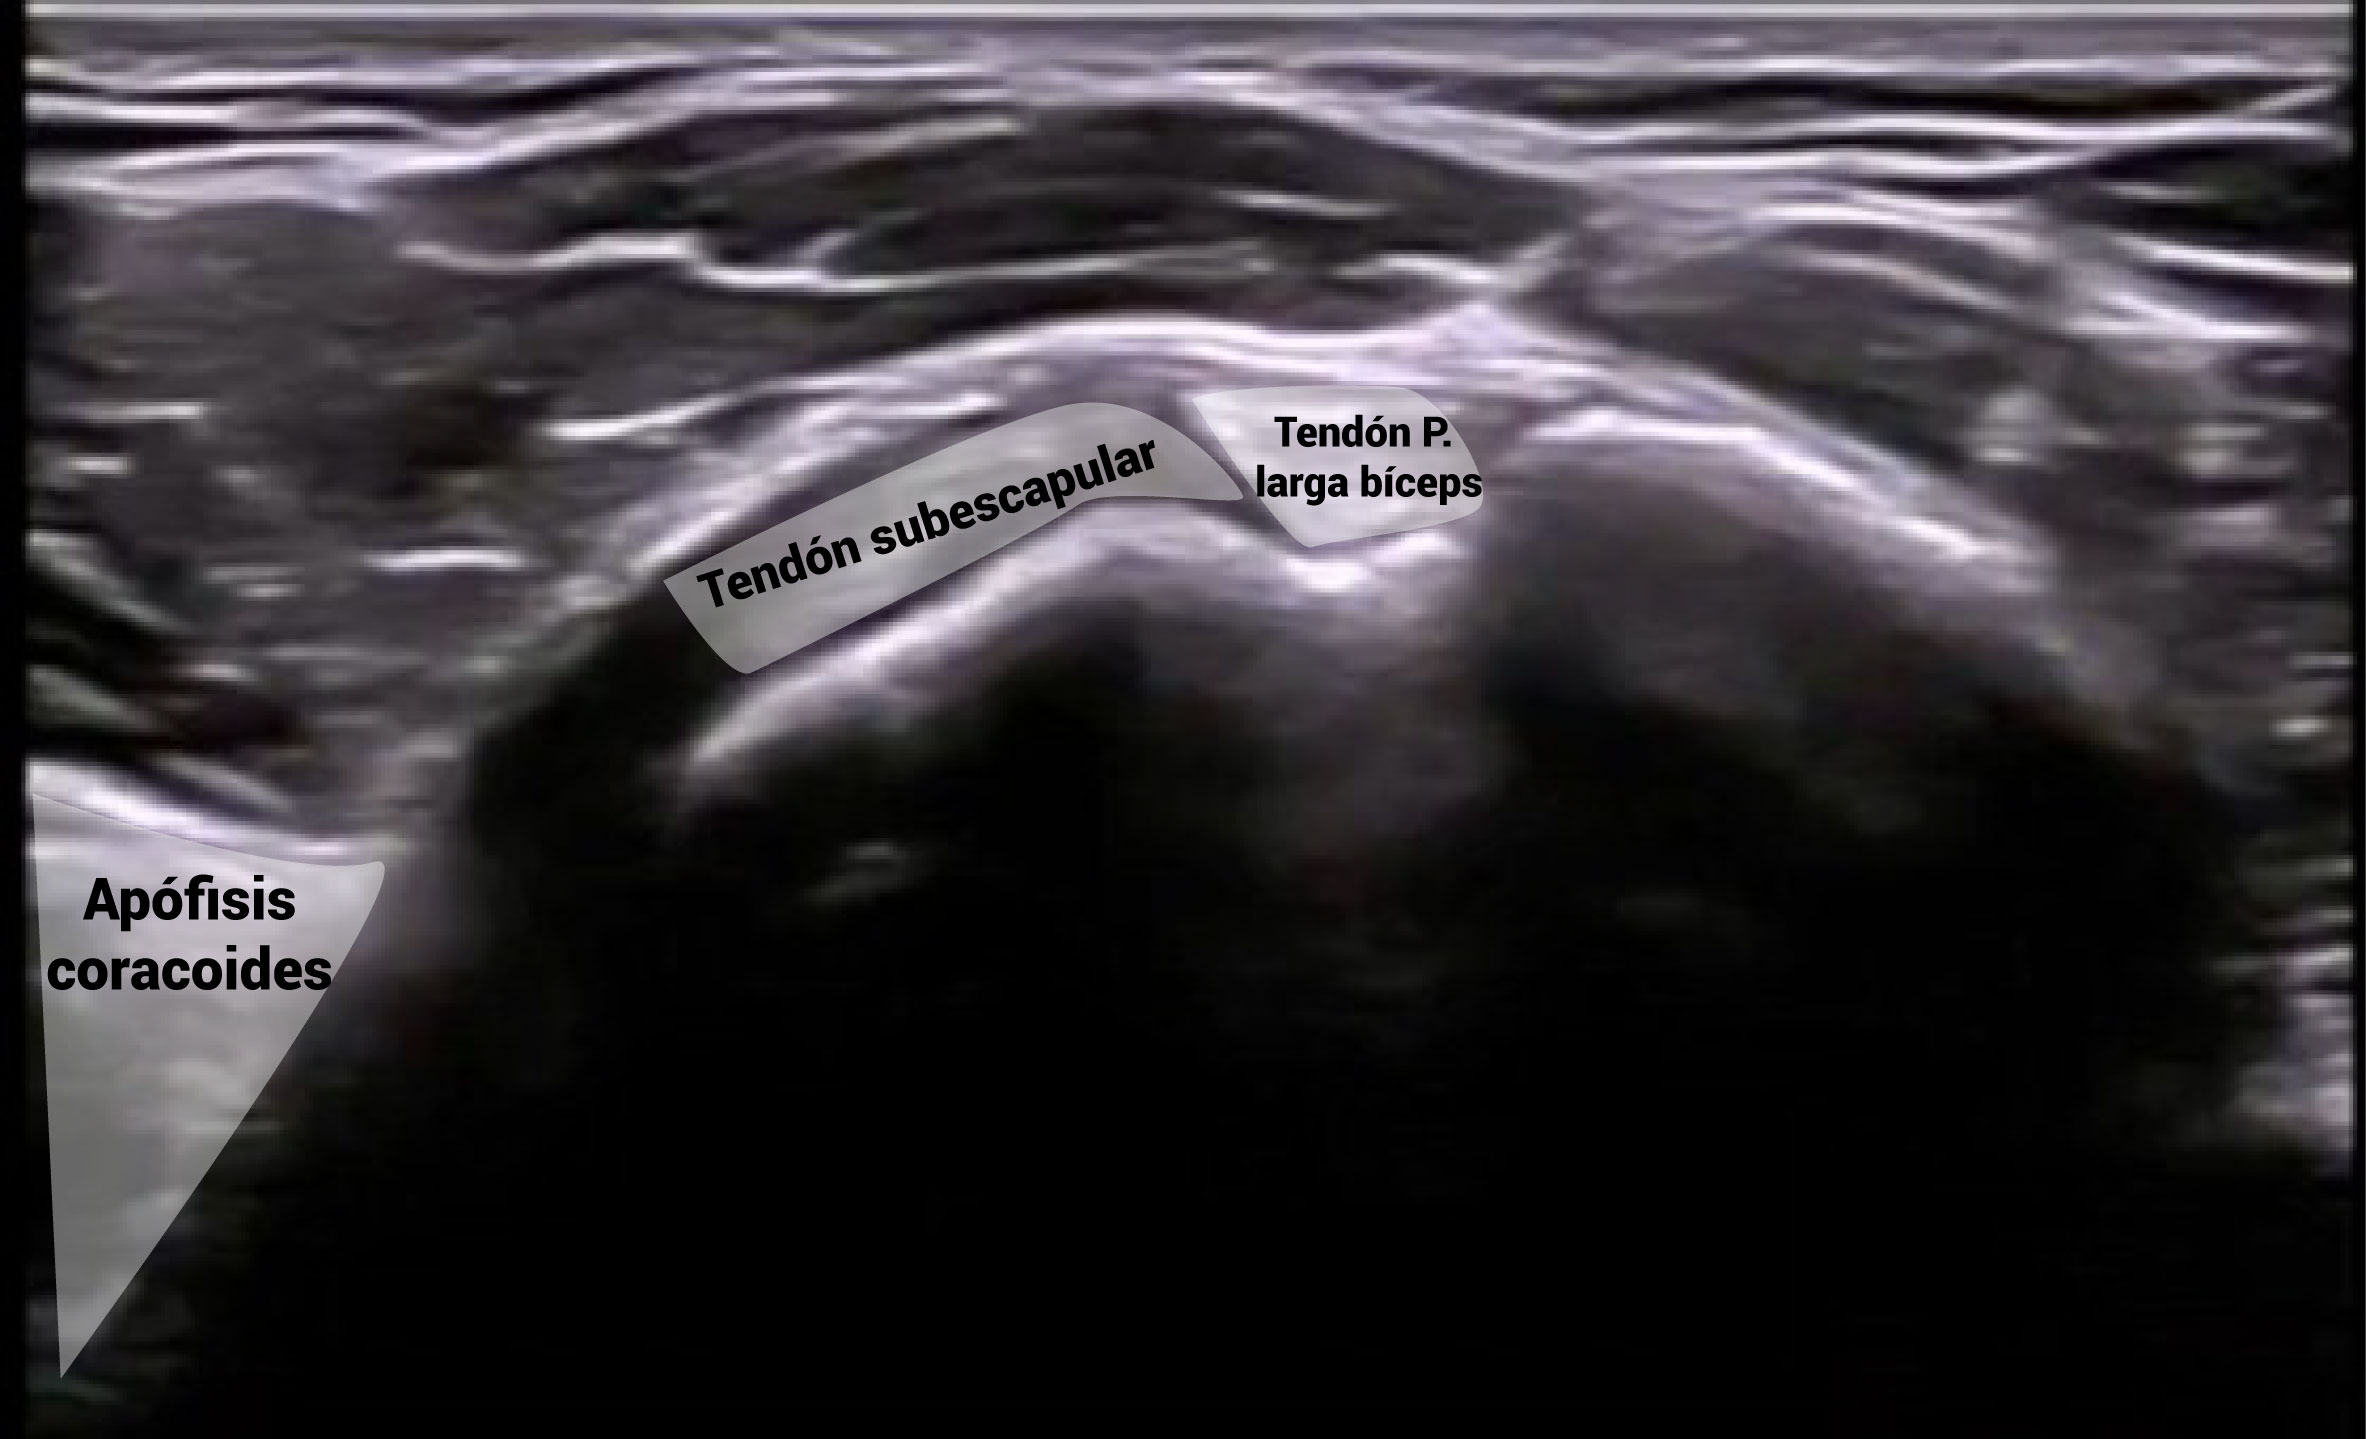

Al igual que la corredera bicipital, la apófisis coracoides es otra referencia anatómica relevante para explorar el tendón subescapular y su vientre muscular.

Provocando rotaciones en el húmero, podremos ver cómo el tendón del subescapular se moviliza por debajo de la apófisis coracoides.